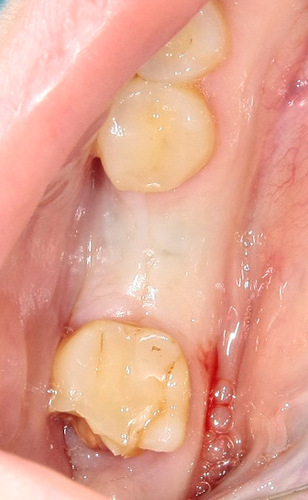

Далее, приступаем к удалению. Неплохо было бы ознакомиться со снимками, для начала — ведь большая часть зуба находится, как известно, вне нашего зрения и видна только на рентгенограммах.

Пара слов о рентгеновских снимках. Нередко слышу два умозаключения:

«на ортопантомограмме корни верхних зубов

находятся в проекции альвеолярной бухты верхнечелюстной пазухи,

поэтому обязательно будет перфорация и ороантральное соустье,

свищ, гайморит, ад и погибель.:»

«на ортопантомограмме корень нижнего зуба мудрости находится близко

(или пересекает) нижнечелюстной канал,

поэтому удаление зуба мудрости приведет к повреждению нижнелуночкового нерва

и последующему онемению половины челюсти, губы и подбородка:»

Разберем подробнее:

Во-первых, панорамный снимок — штука, сильно искажающая пространственное соотношение тканей и структур. Возьмите два листа бумаги с текстом с обеих сторон, сложите их вместе и посмотрите на просвет. Удается ли прочитать текст? Вот ортопантомограмма — примерно, то же самое. Другими словами, сказать по ортопантомограмме о соотношении верхнечелюстной пазухи и корней верхних зубов, равно как и о положении корней восьмерок и нижнечелюстного канала ДОСТОВЕРНО НЕЛЬЗЯ! Поэтому, для такой точной работы как дентальная имплантация, нам нужна компьютерная томография.

Во-вторых, можно просто посмотреть компьютерную томографию, либо сходить в анатомический театр, препарировать труп и убедиться, что корни верхних зубов, чаще всего, не попадают в верхнечелюстную пазуху, а обходят ее по сторонам. А, если и попадают, то между ними и пазухой остается слой костной ткани, надкостницы и слизистой оболочки гайморовой пазухи, которые, при правильной методике удаления, не дадут образоваться соустью. Редкое, очень редкое исключение из этого правила — длительный периапикальный процесс, который приводит к разрушению костной перегородки между лункой зуба и дном верхнечелюстной пазухи.

То же самое касается и нижнечелюстного нерва и восьмерок. Сделав компьютерную томографию мы убедимся, что нижнечелюстной нерв находится гораздо более язычно, нежели корень зуба. А на снимке они, нередко накладываются друг на друга создавая иллюзию пересечения.